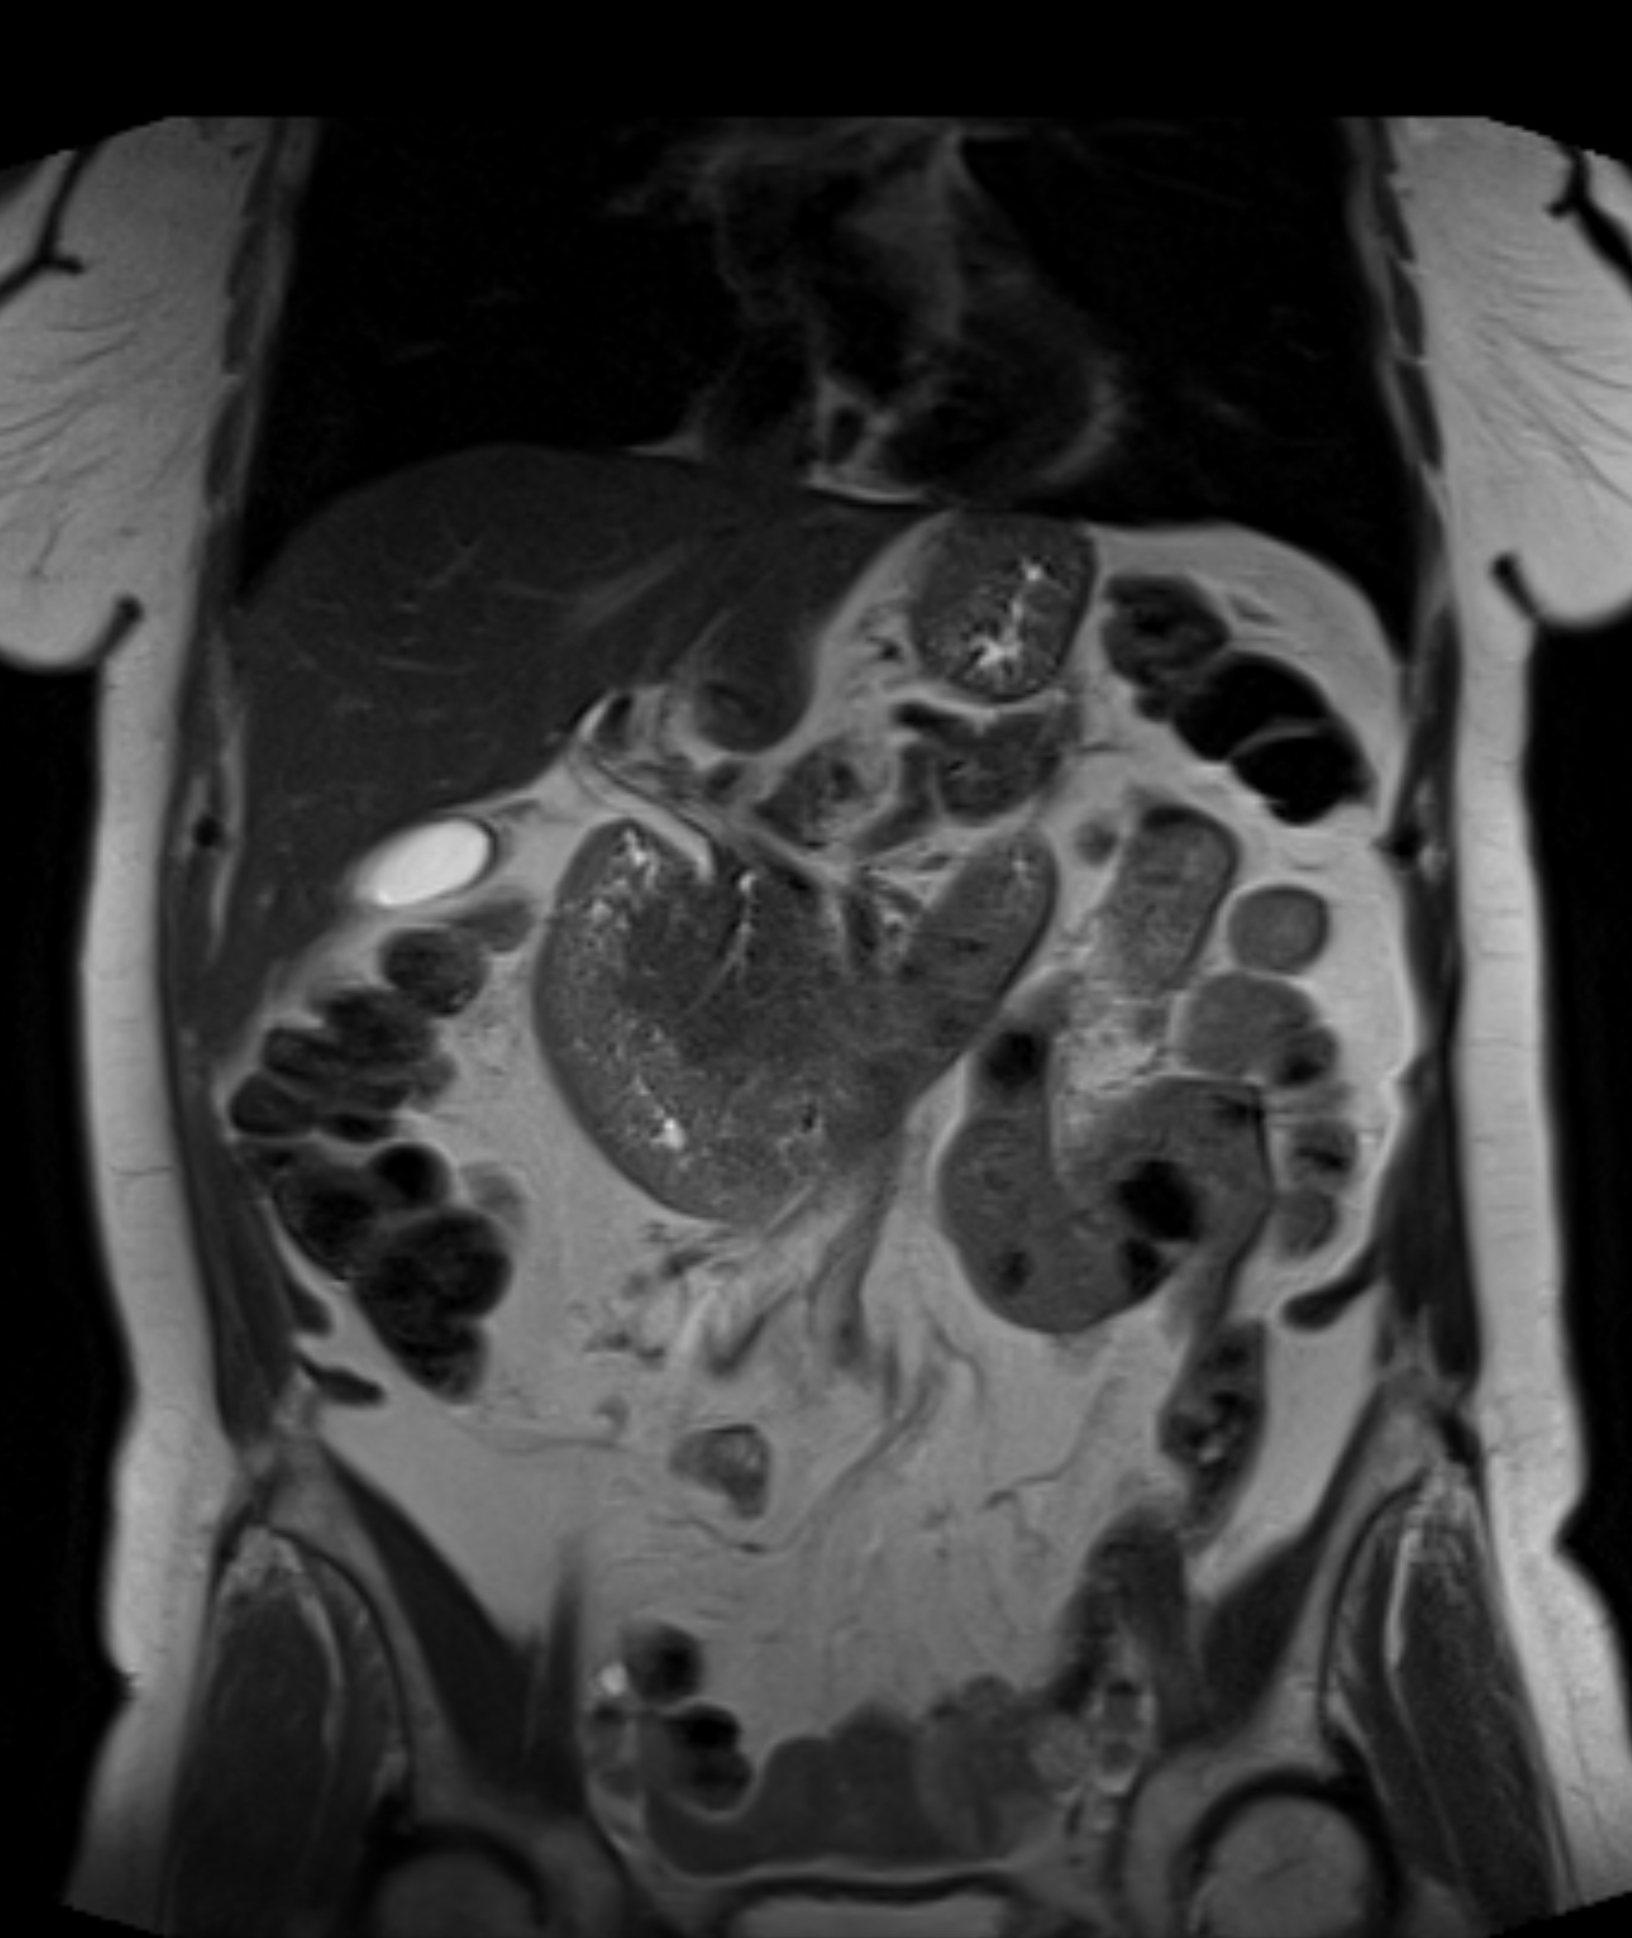

Magnetkameraundersökning av lever, njurar, gallvägar och andra organ i buken

Smärta eller obehag i magen kan bero på många olika orsaker, från godartade cystor och vätskeansamlingar till inflammationer eller tumörförändringar. Eftersom bukhålan innehåller flera av kroppens viktigaste organ används MR buk för att undersöka bland annat lever, njurar, mjälte och bukspottkörtel. MR är en modern och helt strålningsfri metod som ger mycket detaljerade bilder av bukens inre strukturer.

Undersökningen används både vid nytillkomna symtom och vid långvariga besvär där andra metoder, som ultraljud eller datortomografi (CT), inte har gett tillräcklig information. MR buk lämpar sig särskilt väl för att kartlägga organens struktur, upptäcka förändringar och följa sjukdomsförlopp över tid.